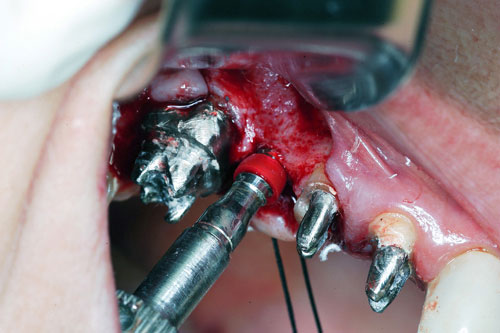

Mientras dichos movimientos ortopédicos se producen (período que supondrá otros seis meses), estudiamos los actos quirúrgicos a realizar en los cuatro implantes que pondremos. De acuerdo al estudio Desatascan realizado observamos tres situaciones diferentes: 1º-El Primer Molar Inferior Izquierdo, lo instalamos mediante Cirugía Minimamente Invasiva , con la aplicación de una Férula Quirúrgica Obtenida de los datos del scanner tratados con un programa de CMI (Cirugía Minimamente Invasiva), previa prueba en un modelo estereolitográfico, ya que la altura ósea era apenas de 9 mm. 2º- El Primer Molar Superior Derecho, se implantará mediante una ligera Elevación Atraumática (Trans alveolar) de Seno una vez logrado el espacio mesio distal necesario. 3º- El Incisivo Central Superior Derecho ausente, cuenta con un sustrato óseo prácticamente inexistente. El espesor de la tabla era de menos de 2 mm. Los caminos posibles a seguir para contar con una Rehabilitación de piezas independientes son dos: Optamos por esta segunda opción por ser menos cruenta y no necesitar de una zona dadora. Técnica esta que pondremos en práctica en dos etapas diferidas: 1º-Incisión horizontal palatinizada, incisiones peri rodetes gingivales e incisiones de descarga. Dilatación que comenzamos con dos incisiones de descarga sobre la cortical vestibular realizadas con disco. y el comienzo de la dilatación propiamente dicha mediante una hoja de bisturí, para luego seguir con un periostótomo . Recién después de alcanzada una cierta separación de la cortical vestibular de la palatina, empezamos con los dilatadores roscados. En este punto podríamos haber utilizado sin riesgos un Implante de 3,8 mm de diámetro, pero a fin de mejorar la estética del pilar emergente decidimos rellenar con material osteoconductor y osteoinductor (BiOss) y cubrir mediante membrana reabsorvible ( Bio Guide). 2º-Implantación seis meses después. Mientras se van cumpliendo los tiempos antes mencionados, y comprobamos reiteradamente la funcionalidad de la oclusión con los provisorios, tomamos impresiones definitivas y construimos primero el maxilar inferior, para definir en primer término la porción inferior de la Guía Anterior., y a nivel posterior Curvas y Microplanos. Para luego realizar los cuadrantes premolar- molar del superior: La espera de la regeneración ósea y sus tiempos pertinentes, más la espera de los tiempos de la implantación, nos obligaron a modificar las etapas del protocolo D.AT.O de manera de mantener la –D- mediante el sector superior de la GA. en provisorios, mientras fuimos resolviendo en forma definitiva los demás sectores. Ya pasados los meses necesarios para recrear un hueso adecuado en el área del Incisivo Superior Derecho, procedemos a resolver la implantación de dicha zona, observando que todo el esfuerzo dedicado al mismo había sido inútil, ya que la formación de hueso se produjo minimamente. Cuatro meses después tomamos impresiones del sector Antero Superior de la Guía Anterior, incluyendo el arrastre de un transfer . Seguimos modelando la encía con un nuevo juego de provisorios. Y se construye entonces el sector superior de la Guía Anterior. Se efectúa un control radiográfico a los 6 meses. Se ha intentado mostrar en esta Rehabilitación, que a pesar de las distintas circunstancias de cada paciente, siempre debemos tener en cuenta la necesidad de ejercer la DESOCLUSIÓN del caso como prioridad número uno, para luego perseguir la ALINEACIÓN TRIDIMENSIONAL de las arcadas y obtener así una OCLUSIÓN equilibrada. D.AT.O. ES EL PROTOCOLO QUE DEBEMOS SEGUIR EN TODA REHABILITACIÓN. BIBLIOGRAFÍA 1)William Mc Horris,B.S.,D.D.S. Oclusión. Con especial énfasis sobre :El rol funcional y parafuncional de los dientes anteriores. 2)Von Spee , Craff(Anatomista alemán, describió la curva de compensación de la articulación de molares y premolares).CURVA DE SPEE 1.89 3)Stuart,D.”Some aspects of the inervation teeth.”Procedings of Royal Society of Medicine.20:1675,19274)Muhleman,H. y Savdir,S”Tooth movility-its causes and significance”Journal of Periodontology ,36:153,Marzo ,Abril,1965. 4)Muhleman,H. Y Savdir,S”Toothmovility its causes and significance” Journal of Periodontology,36:153,marzo,abril,1965. 5-Oclusión y Diagnóstico en Rehabilitación Oral. 6-Anatomia Odontológica. 7-A contribution to the study of the movementes of the mandible. 8-Celenza F.W, Nadeskin J.F.,Oclusión.Situación actual. 9-D´Amico 10-Dawson P.E. 11-Huffman –Regenos. 12-Hobo S.-Takayama H.A. 13-Lucia V.O 14-Mc Horris. 15-Mc Horris. 16-Stuart C. 17-Vartan Veshnilian 18-Alvarez Cantoni H. AUTOR:Ratificación del Protocolo en Rehabilitación Bucal a pesar de las incidencias propias de cada caso clínico. A propósito de un caso.

Verificamos también el escaso ancho crestal, lo que nos obliga a utilizar dilatadores roscados y un osteótomo para elevar inicialmente la membrana de Schneider.

Elevación de membrana mediante periostótomo

Elevación de membrana mediante periostótomo